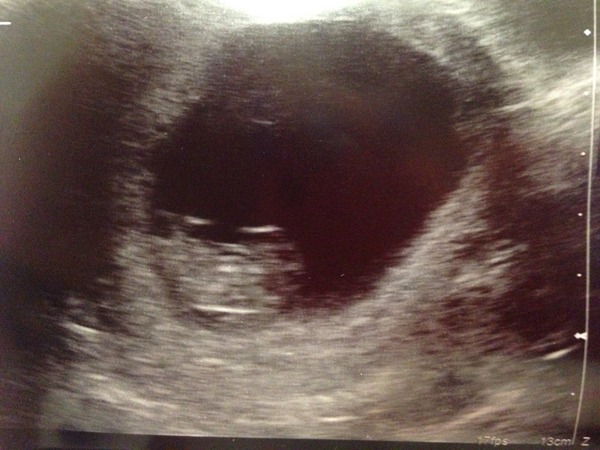

Great news on the scan as well Birdbrain